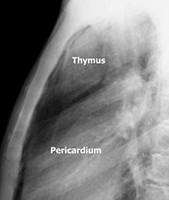

To facilitate the dissection and to shorten operative time, adjuvant pneumomediastinum is routinely performed 24 hours before the operation by introducing a Veress needle under local anesthesia at the level of the suprasternal notch, behind the posterior wall of the sternum [2]. Afterwards, 400 to 600 mL of air is insufflated in a sterile manner at a rate of 25 mL/min. Through this simple and safe maneuver, the thymus is progressively separated from the surrounding structures (Figure 1).

The dissection is begun inferiorly by incising the mediastinal pleura along the anterior border of the phrenic nerve (Figure 3). Because of the preoperative pneumomediastinum, the mediastinal adipose tissue is embedded with air and the thymus is already partially separated from the pericardium and from the sternum. As a result, the dissection proceeds more rapidly and easily, mainly by blunt maneuvers, with the aid of two pledgets.